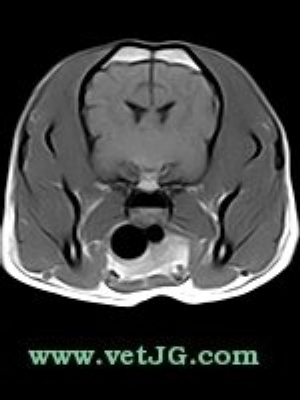

RESONANCIA MAGNÉTICA

AXIAL

SAGITAL

DORSAL